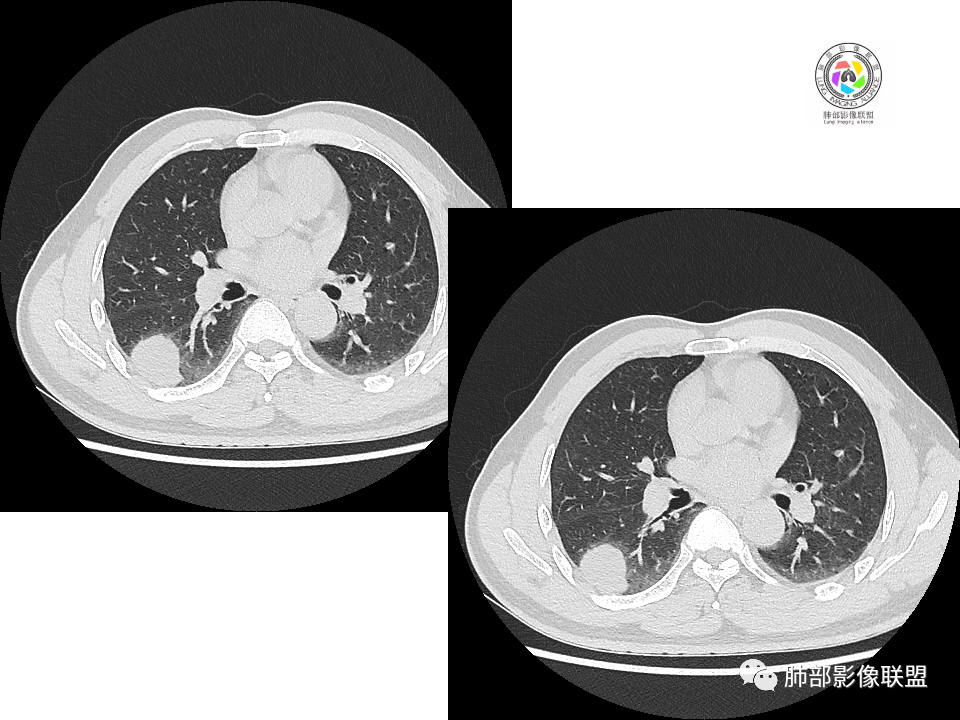

2.右肺下叶背段胸膜下块影,边界清楚光整,上下极见磨玻璃晕,未见明显分叶毛刺和棘状突起,未见胸膜凹陷或胸壁侵入。密度均匀,轻度不均匀强化。未见支气管进入。

3.右肺中叶外侧段胸膜下散在小片影,磨玻璃密度为主,边界不清,支气管相关。符合炎性特征!

4.右肺下叶基底段支气管血管束旁小结节影,边界清楚,强化不明显。注意,这结节在“遥远的”基底段。

关于结节型隐球菌

1、普通人隐球菌感染的时相:初期的隐球菌感染周围有晕,晕从多变少,或包裹,或吸收,结节实性区可迅速变大。后期(慢性期)的隐球菌周围无明显晕征,边界较清楚。

2、有些模糊晕消失慢的原因:隐球菌对周围肺组织破坏相对不重,周围所供应的营养不多,增殖也不快,呈局部相安无事的状态。隐球菌消灭之后,肺泡间隔的炎症细胞及间质恢复更慢,所以经常能见到隐球菌外面隐约带细丝的模糊影。

3、卫星灶与“蘑菇兄弟”:诊断隐球菌时,建议找卫星灶,卫星灶可以在遥远的地方。可以是遥远地方的微小结节——“小蘑菇兄弟”。有些远处的卫星灶,通常是不规则饱满实性的,晕征不明显。隐球菌的卫星灶非常“隐”,但发现率高达60%多,诊断价值高。

4、卫星灶距离远的原因:隐球菌卫星灶常很远,推测:一次空气来源隐球菌感染进入双肺多处,部分定居繁殖;距离近的隐球菌“蘑菇兄弟”常常是二次感染。

5、周围毛刺纤维、边缘形态等:坏死包裹会使得结节变圆;结节多缺乏明显的分叶征,缺乏局部突出生长能力;如果出现分叶,是由多处肉芽肿中心形成。没有坏死的局限化,结节只是凑合在一起,常呈方形征;毛刺进入晕区(概念源自南边老师),毛刺较短、较软;周围的晕吸收后,会留下不规则边,外面常残留丝状条索;收缩力较弱,临近胸膜对胸膜牵拉不明显。

6、隐球菌的毛刺消失于晕区的解释:隐球菌结节周围有间质淋巴细胞增多,肉芽肿性炎延伸,以及纤维组织增生,形态并不规则,不是因为收缩力。

7、其他:隐球菌实性区相对腺癌更实,一旦实变里面就没空气,胸膜牵拉线(小叶间隔)拉的不太紧。